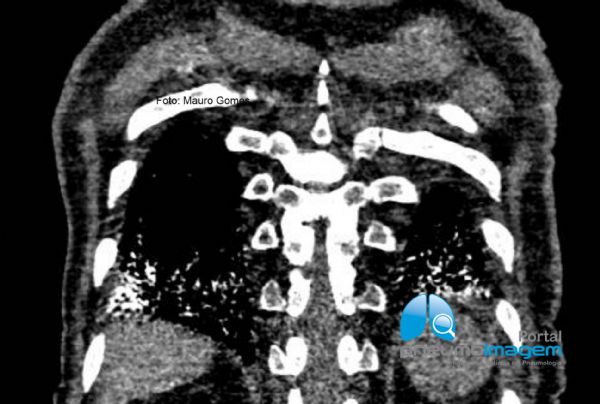

Observe que nos cortes inferiores há áreas em vidro fosco e as lesões tendem a predominar do lado esquerdo, o que pode sugerir relação com aspiração noturna devido ao decúbito.

In the lower sections there are areas of ground glass and the lesions tend to predominate on the left side, which may suggest a relationship with nocturnal aspiration due to the decubitus position.